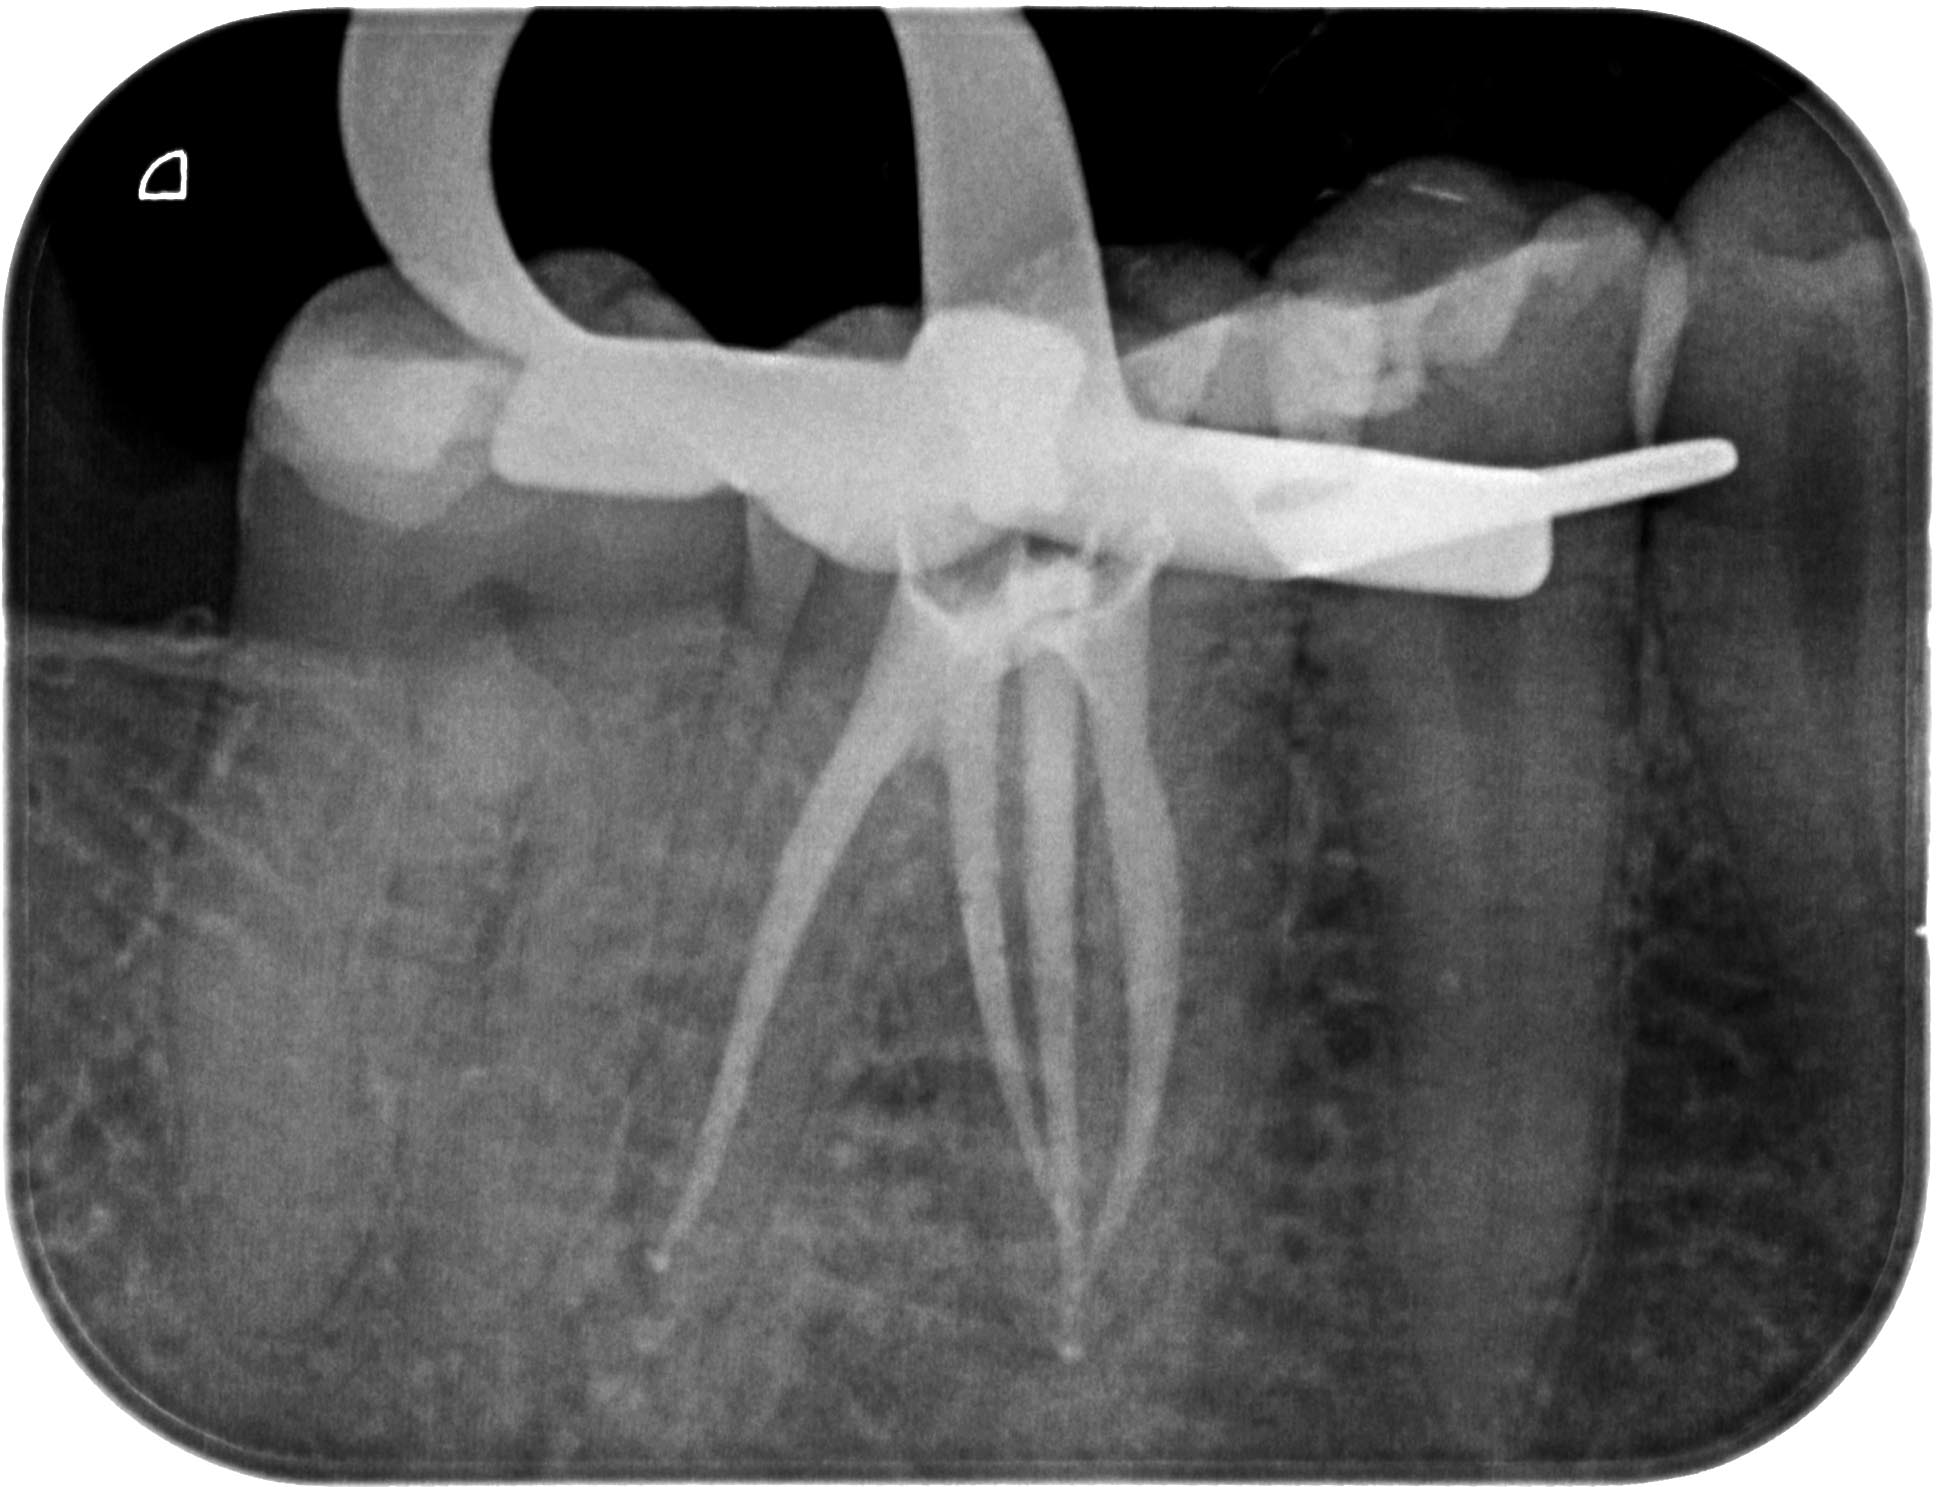

EP_46-1-2

1936 × 1487

Schwieriger UK- Molar (1 von 3)